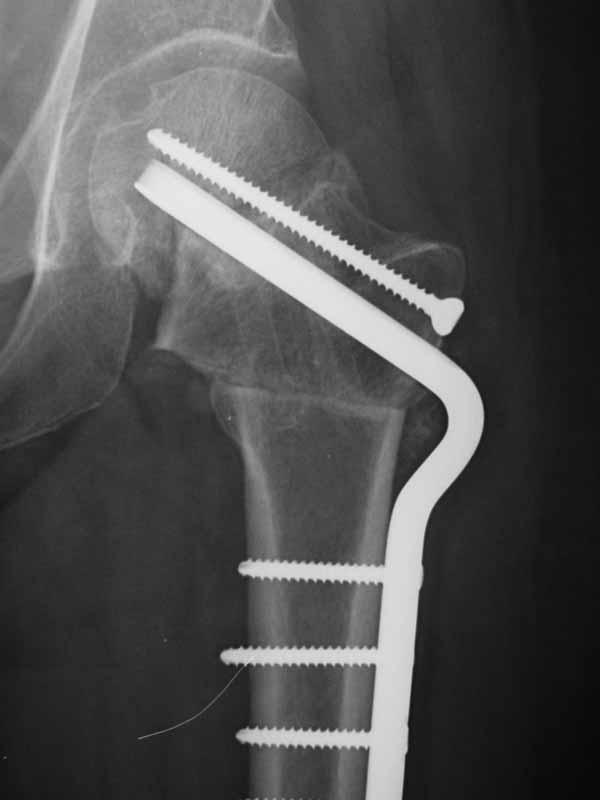

If I were u , a DHS will be used to fix it . And I will tell the patient not to weight bearing from now on. It will accelerate the aseptic necrosis of the femoral head.

dhs will not correct improper improper biomechanical environment and may further compromise vascular integrity

establish vascular status via mri and if viable follow with proximal valgus osteotomy

case provided s/p failed fixation